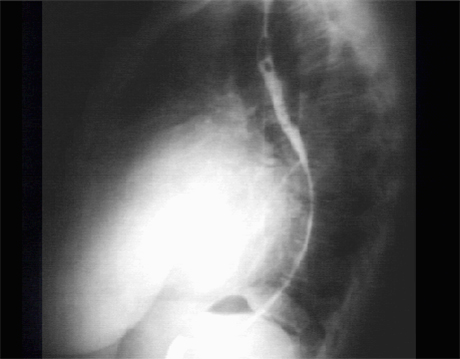

PA

The lateral view with barium swallow, demonstrates marked posterior displacement of the esophagus by the giant left atrium.